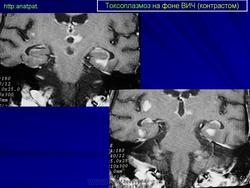

Токсоплазмоз у ВИЧ - инфицированных

Церебральный токсоплазмоз

Токсоплазмоз